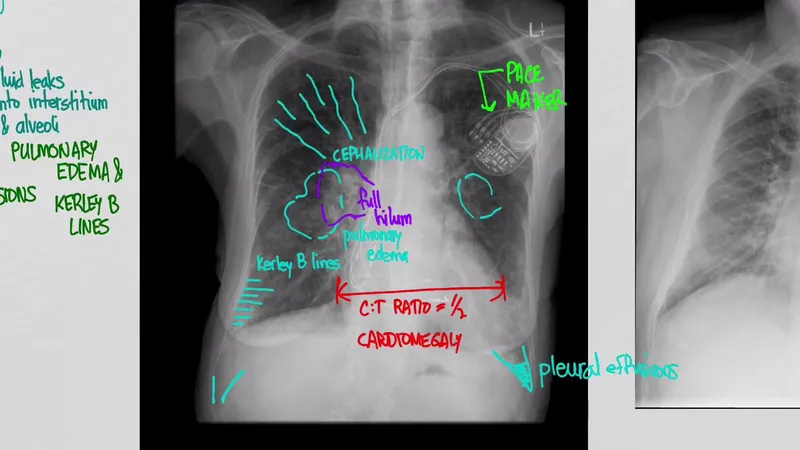

| Chest X-ray | 5-10 minutes | 80% | 85% | Congestion assessment |